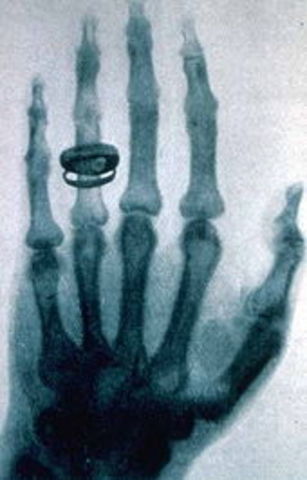

Histoire de la découverte des rayons X et de leur application en médecineEn 1895, le physicien allemand Wilhelm Röntgen alors âgé de 50 ans étudie le rayonnement cathodique avec des tubes de Crookes. Il s’intéresse plus précisément à la pénétration des rayons dans le verre. Il a déjà été constaté à l’époque que les rayons cathodiques peuvent franchir la paroi du tube et pénétrer de quelques centimètres dans l’air.

Dans la soirée du 8 novembre, au cours de ses travaux préliminaires il décide de recouvrir le tube d’un cache en carton noir. Il constate alors qu’un écran